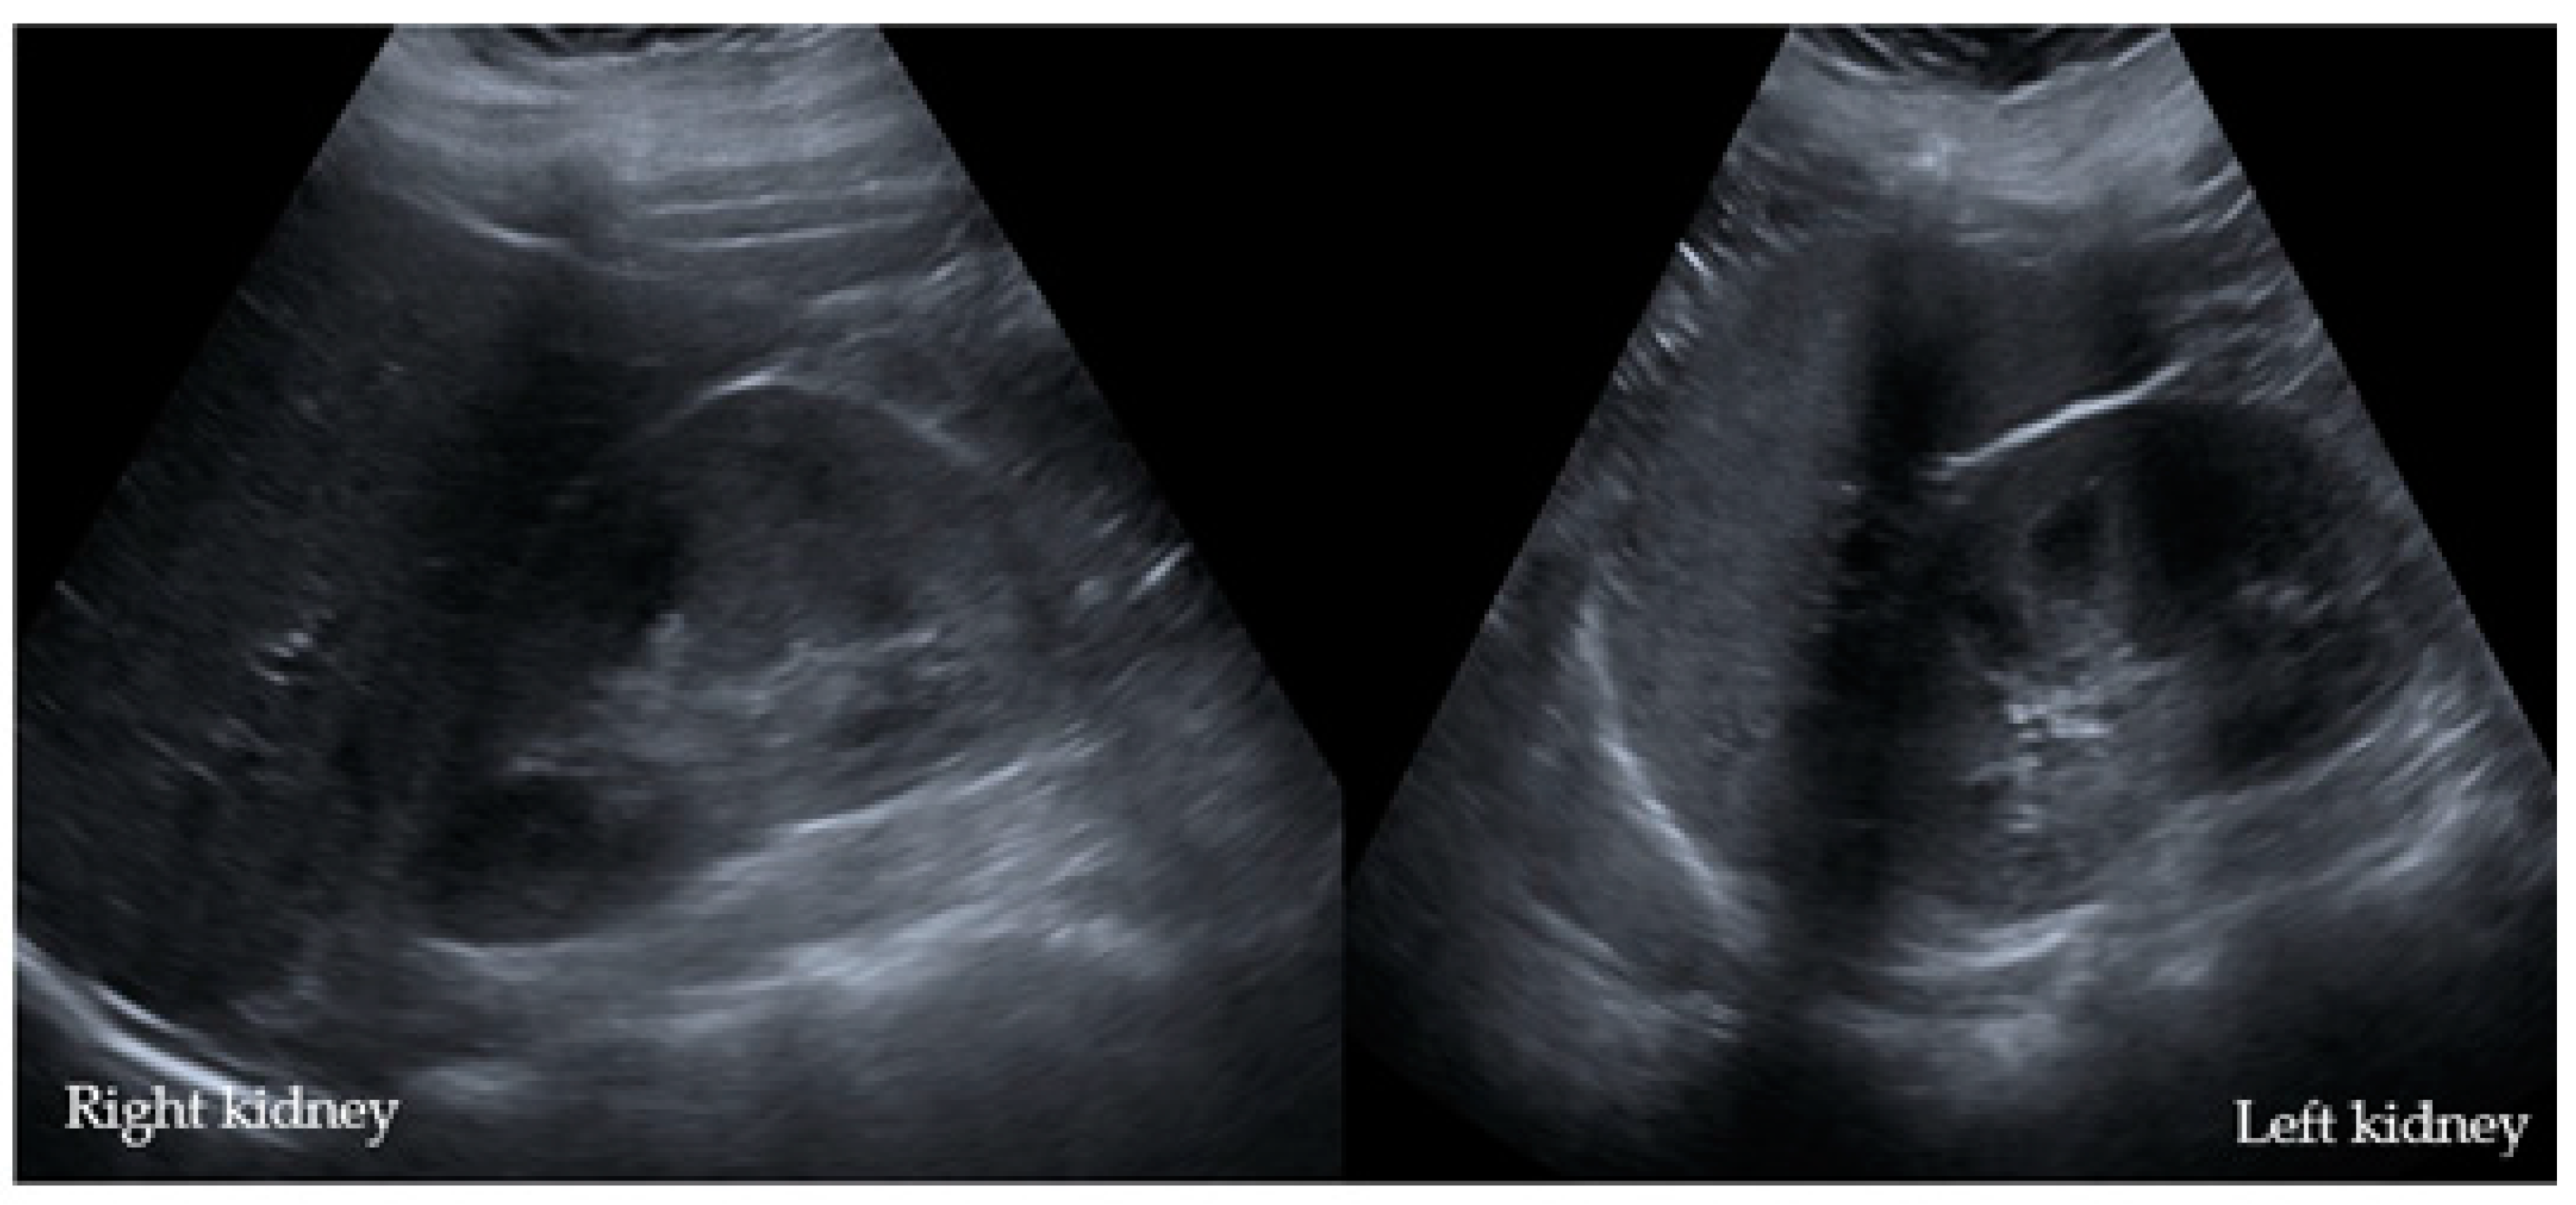

Abdominal sonography showed a bilateral echo-rich region of the renal cortex on both sides (Figure 4).

Figure 4. An ultrasonography of the kidneys of Case II°. Both kidneys presented mild echogenic accentuation of the parenchyma with consecutive increased corticomedullary differentiation.